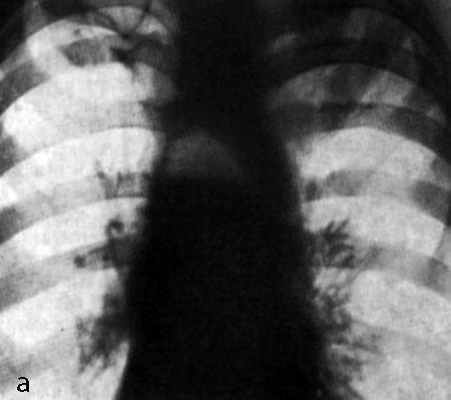

Обычная рентгенография грудной клетки в двух проекциях может выявить косвенные признаки медиастинита, такие как подкожная эмфизема, латеральное или переднее отклонение трахеи и наличие плеврального выпота.

Проводится тщательное рентгенологическое обследование (рентгенография грудной клетки, томография, рентгенография пищевода, пневмомедиастинография). Рентгенологически при медиастините может выявляться расширение тени шеи и средостения, эмфизема средостения, пневмоторакс, гидроторакс, уровень жидкости в средостении, пищеводные свищи.

- обзорная рентгеноскопия и –графия органов грудной клетки (обязательно в двух проекциях- передне-задней и боковой) – с ее помощью фиксируют эмфизему средостения (раздутие воздухом, попавшим сюда через дефекты тканей), а на более поздних этапах – признаки гноя;